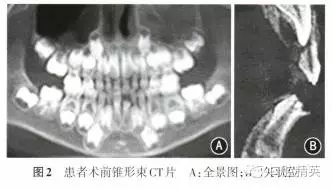

患者男性,7歲10個月,因左下乳前牙脫落后長出一牙尖半年余要求治療,于2014年11月至南昌大學附屬口腔醫(yī)院口腔頜面外科門診就診?;颊呒韧w健,無牙病及外傷史,無家族史。體格檢查示身體發(fā)育正常,口腔檢查:II缺失,l缺牙區(qū)唇側可見一圓錐形牙尖突出于牙齦表面,色澤正常(圖1);66616已萌出,混合牙列,余未見明顯異常。錐形束CT檢查示1唇側鷹爪狀畸形尖,直徑約1.0 mm,長度約3.2 mm,尖端離切緣約2.6 mm,不與髓腔相通;切緣形態(tài)亦發(fā)育異常,近髓角;牙根發(fā)育至根長1/2左右,根尖呈喇叭狀;無先天性牙缺失及額外牙(圖2)。